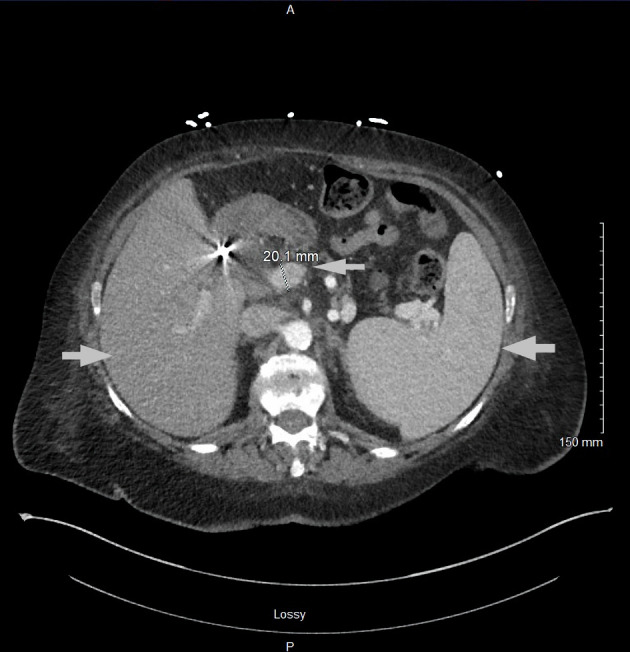

肥大细胞白血病(MCL)是一种罕见的侵袭性系统性肥大细胞增多症(SM),通常累及骨骼。这通常表现为骨质疏松伴局灶性溶骨病变和病理性骨折。成骨细胞(硬化)病变在MCL中很少见。椎体是最常见的骨受累部位,轴骨以外的病变极为罕见。以成骨细胞病变为表现的MCL在文献中已有报道,然而,在阑尾骨骼中没有成骨细胞病变的报道。在此,我们报告一例罕见的急性白血病MCL,表现为弥漫性成骨细胞/硬化性骨病变,累及肋骨、胸椎、腰椎和骨盆,无病理性骨折。

Mast cell leukemia (MCL) is a rare and aggressive form of systemic mastocytosis (SM) that commonly involves the bone. This often presents as osteoporosis with focal osteolytic lesions and pathological fractures. Osteoblastic (sclerotic) lesions are rarely seen in MCL. The vertebral bodies are the most common site of bone involvement, with lesions outside of the axial skeleton being extremely rare. MCL presenting with osteoblastic lesions has been reported in the literature, however, there are no reported cases of osteoblastic lesions in the appendicular skeleton. Here we report a rare case of acute aleukemic MCL that presented with diffuse osteoblastic/sclerotic osseous lesions involving ribs, thoracic spine, lumbar spine and pelvis without pathological fractures.